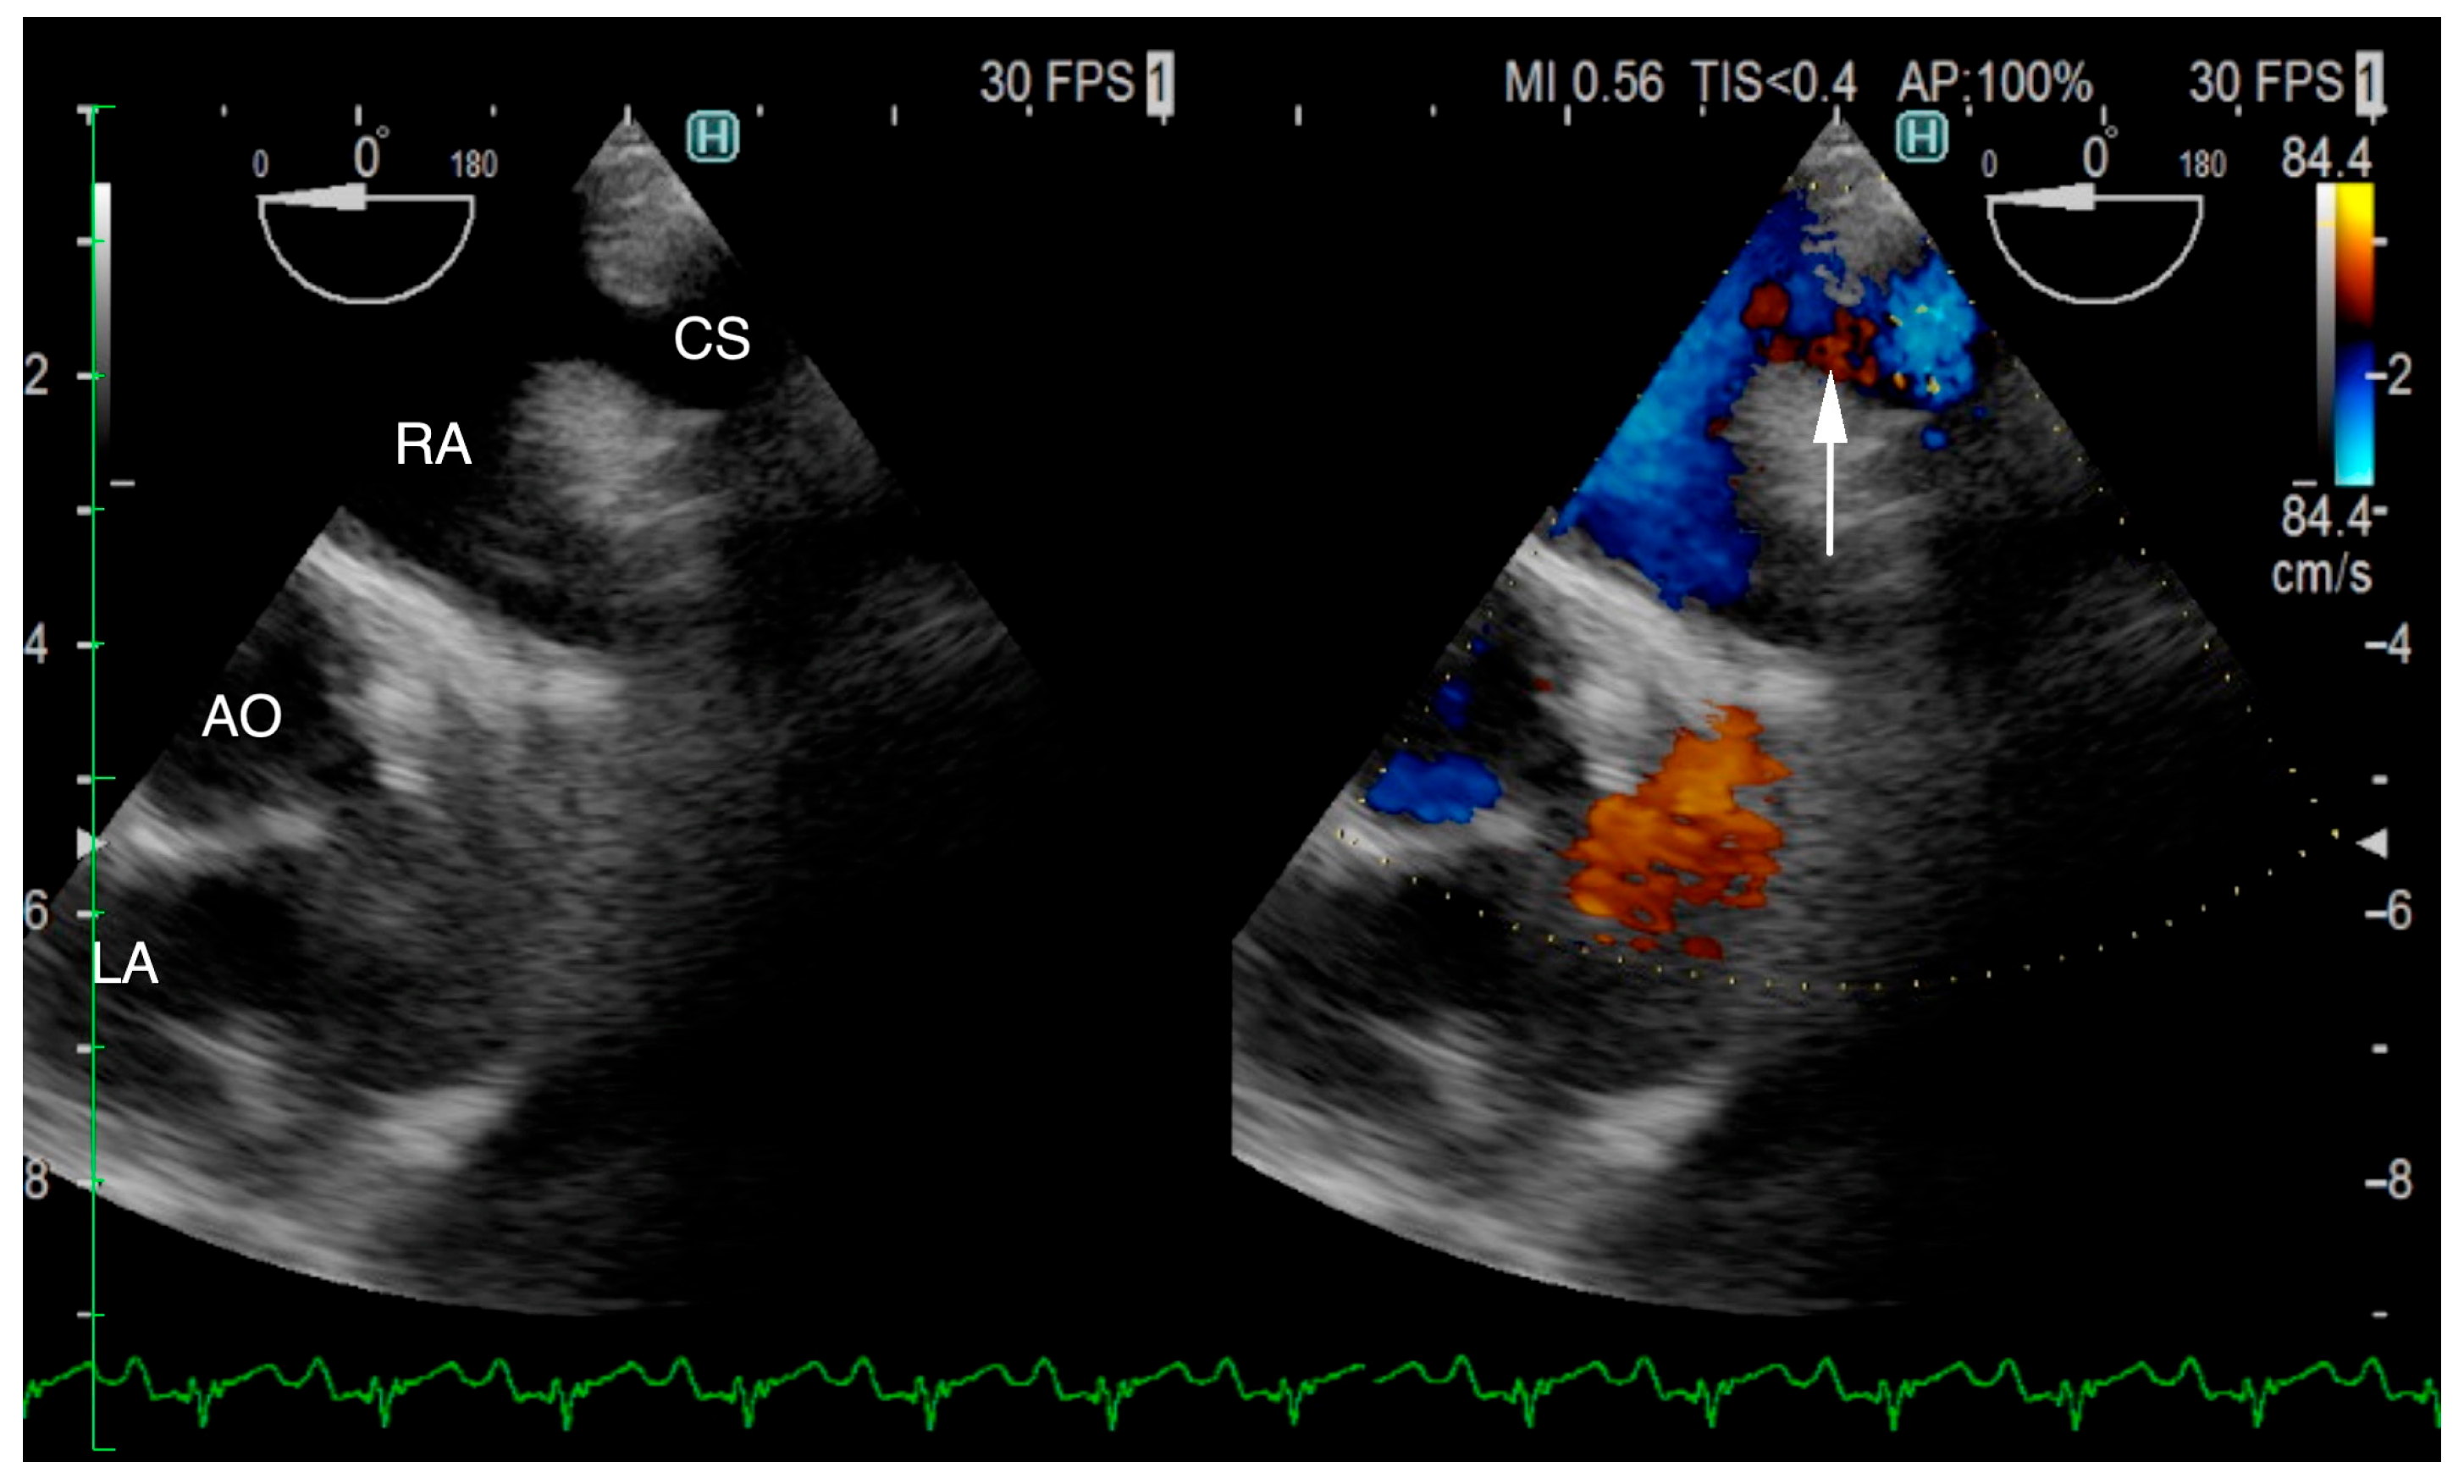

The ECG-gated CT showed communication between the LA and RA via the CS (Figure 2a). An enlargement of the CS, where the coronary artery measured 0.8 mm in diameter, whereas the CS measured 11.6 mm, was observed (Figure 2b). The CS drained normally into the RA; however, an ostium to the LA was seen, leading to the diagnosis of UCSS (Figure 3a). Under general anesthesia, TEE was also conducted using LISSENDO 880LE (Fujifilm Ltd., Tokyo, Japan) equipped with the 8–2 MHz phase array transesophageal probe (Fujifilm Ltd., Tokyo, Japan). With TEE, it was possible to identify the shunt as an abnormally large CS running along the cardiac wall (Figure 4).

Figure 4. Transesophageal echocardiography (TEE) shows the coronary sinus (CS) draining into the right atrium (RA) (arrow). The CS is typically not visible on TEE; however, in our patient, it is seen, suggesting that it is dilated due to an unroofed segment or an opening in the CS. CS, coronary sinus; RA, right atrium; AO, aorta; LA, left atrium.